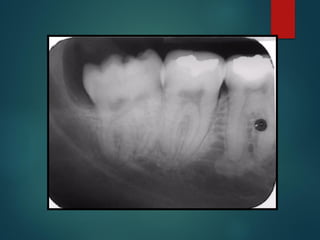

Clasificación Radiográfica

De Las Caries

 Incipiente de esmalte

 De esmalte

 Dentinaria superficial

 Dentinaria profunda

 Sobreproyectada en cámara pulpar

 Penetrante